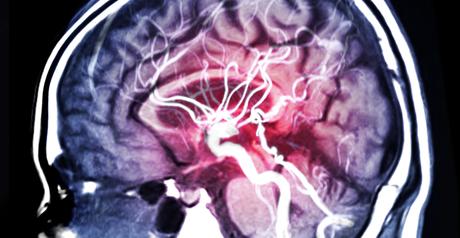

Un diabète de type 2 préexistant est lié à de moins bonnes performances cognitives après un accident vasculaire cérébral (AVC), soulignent ces chercheurs de l’Université de Nouvelle-Galles du Sud (Australie). Ces travaux, présentés dans Stroke, une revue de l’American Heart Association, confirment des preuves déjà solides d’une association entre le diabète de type 2 et une déficience cognitive, alertent à vérifier la capacité du patient, post-AVC, à contrôler son diabète et incitent à détecter les premiers signes de prédiabète afin d‘éviter ou de retarder ces complications cérébrales et cognitives.

Ainsi, les personnes atteintes de diabète de type 2 présentent de moins bonnes performances cognitives 3 à 6 mois après un AVC, par rapport à des patients non diabétiques. Au-delà relation entre diabète et cognition est complexe : le diabète de type 2 augmente le risque d’AVC et a déjà été associé à des troubles cognitifs ainsi qu’à un risque plus élevé de démence.